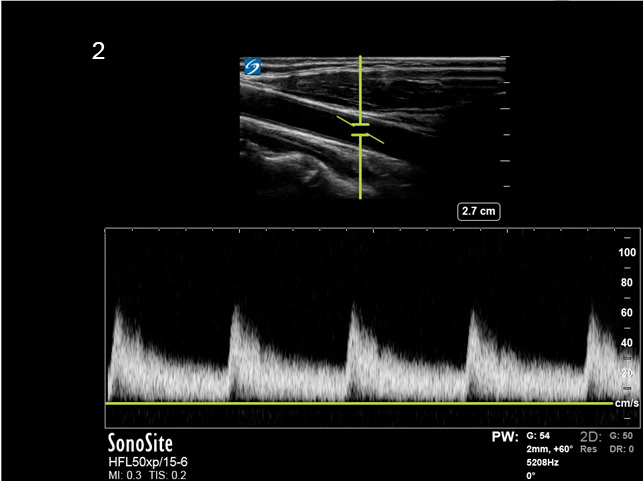

Instrumentation Pulse Wave Doppler High Gain Image